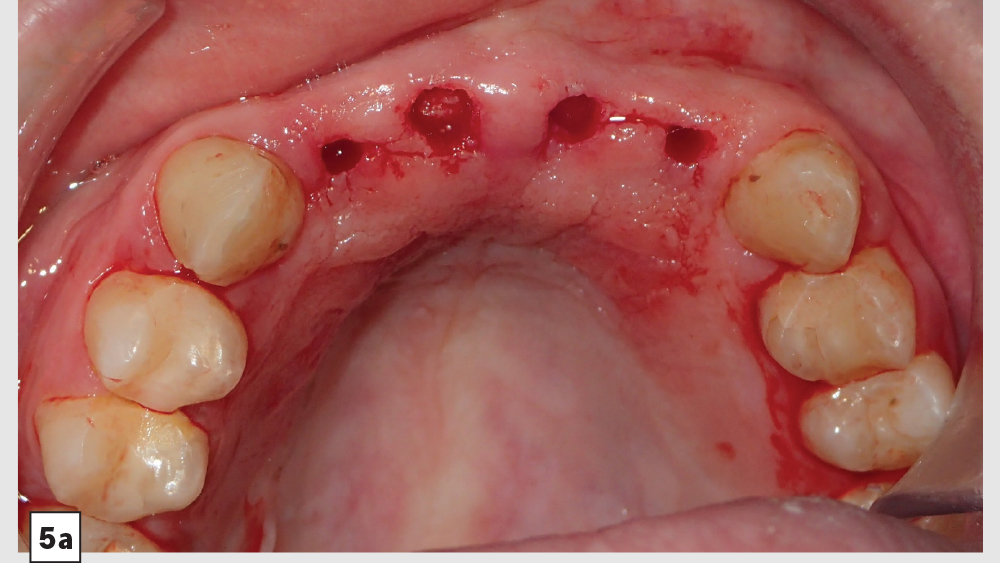

Digital treatment planning (DTP) with the team at Glidewell Laboratories allows me to ensure that implants are precisely placed, with full consideration given to the desired esthetics of the final restorations. But there was another unique element involved in planning the case described below: While it was esthetics that caused the patient to seek treatment, his career as a glass blower required his implants to be placed in functionally ideal positions. The potential complexity of these multiple requirements solidifed my decision to approach his case with implant positioning predetermined via DTP.

This patient came to me with four missing anterior teeth in positions #7–10. He had been missing these teeth for some time and was wearing a temporary denture to address the cosmetic issue this created. When he came to my practice, he was in a financial position to solve the problem permanently with implant restorations. Based upon the anterior space available and the fact that the patient’s surrounding tissue was in good health, I chose to move forward with Hahn™ Tapered Implants and BruxZir® Esthetic restorations.